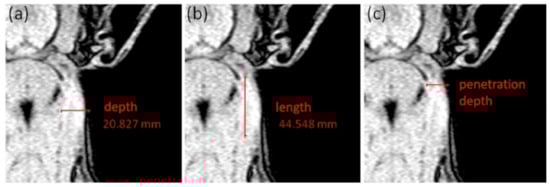

- Length and depth measurements: Additionally, the MR image with the largest area of hyperintense tissue of each animal and each examination day was analyzed regarding the maximum extent of local reaction in depth and length (in mm; see Figure 2a,b). Therefore, the deepest point at the IS showing a bright signal increase was measured from the skin side and represents the maximum depth (mm) of the local reaction (Figure 2a). The maximum length (mm) of the local reaction was calculated by measuring the cranio-caudal distribution of the bright signal increased region (Figure 2b). Furthermore, the injection site was defined as the point, where the signal increase starts near the ear base. At that point, the penetration depth was measured (in mm; see Figure 2c).